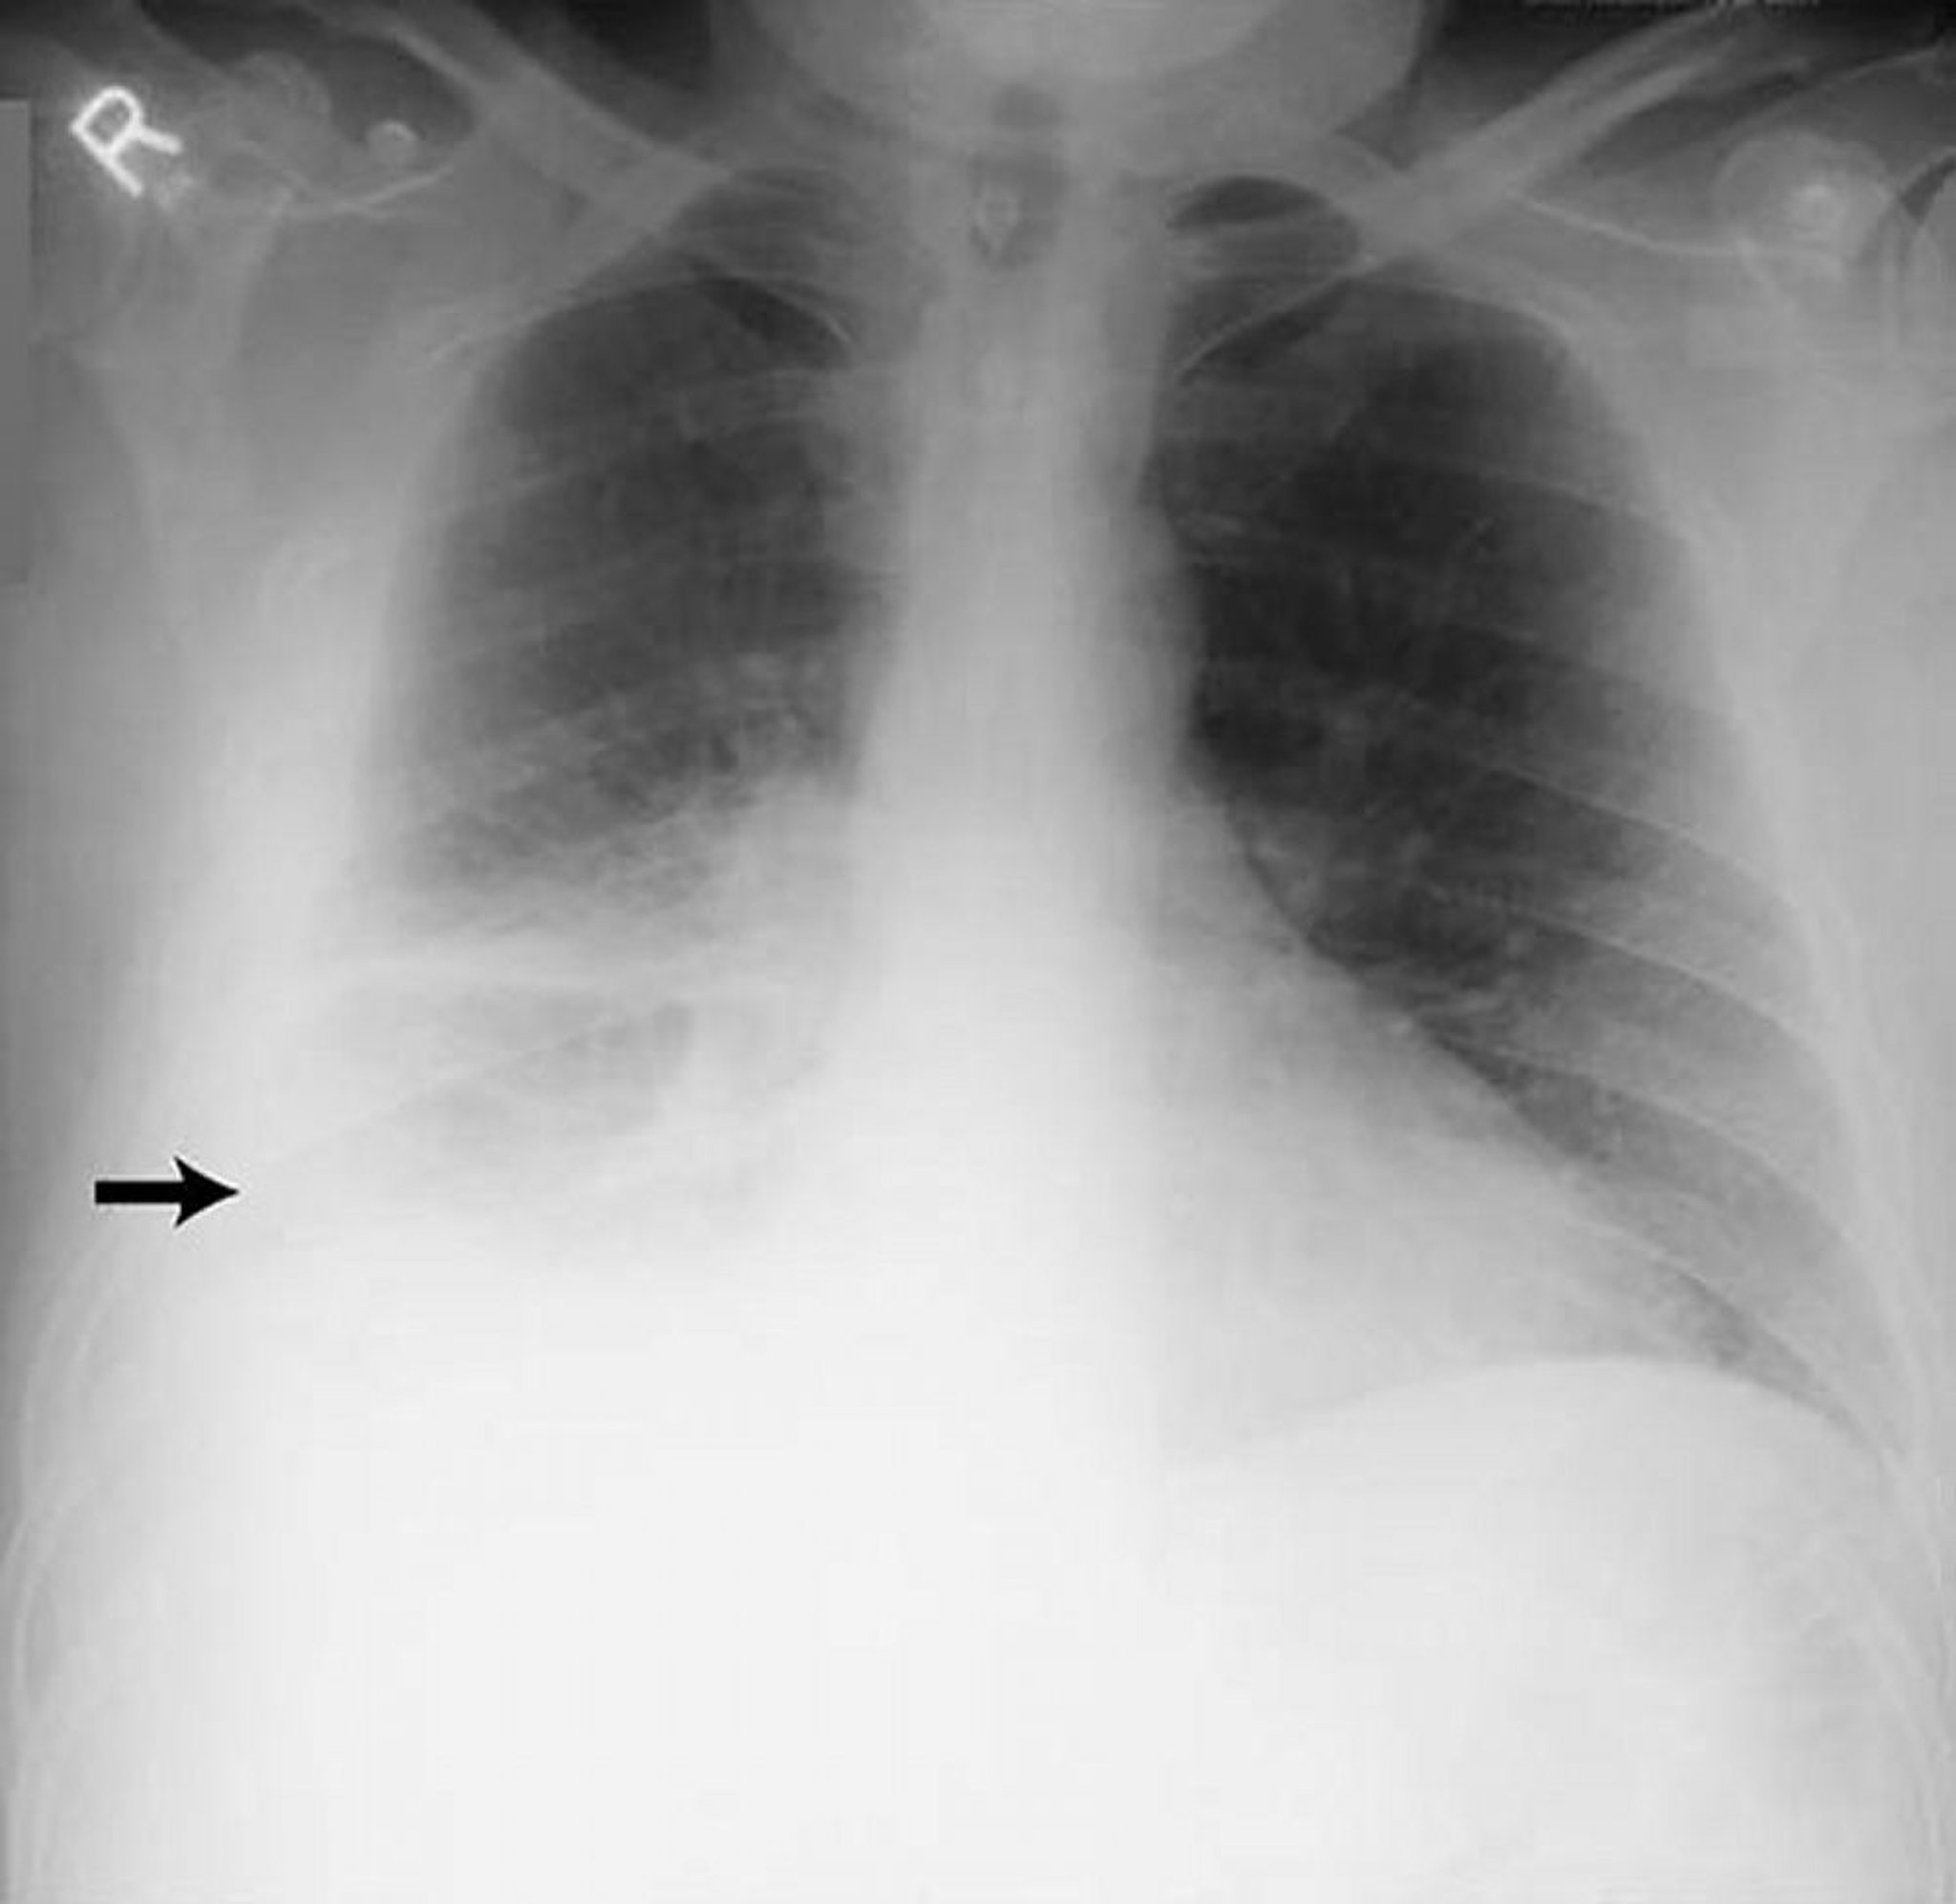

Derrame pleural — extenso

Esta imagem mostra grande derrame pleural à direita (seta) em paciente com pleurisia reumatoide.

By permission of the publisher. From Huggins J, Sahn S. In Bone's Atlas of Pulmonary and Critical Care Medicine. Edited by J Crapo. Philadelphia, Current Medicine, 2005.